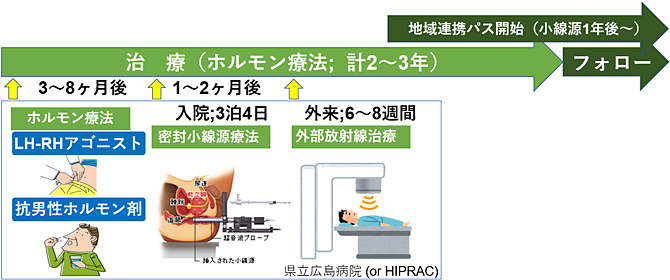

トリモダリティ療法の実際の流れは?

トリモダリティ療法終了後、PSAフォローは地域のかかりつけ医で継続して、長期間行います。